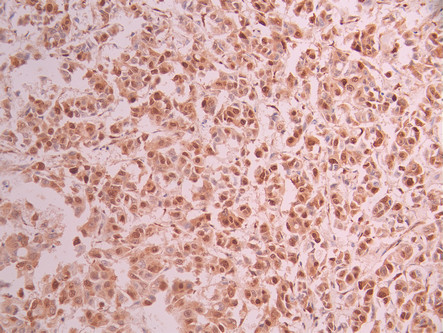

IHC image of CSB-RA821323A0HU diluted at 1:100 and staining in paraffin-embedded human breast cancer performed on a Leica BondTM system. After dewaxing and hydration, antigen retrieval was mediated by high pressure in a citrate buffer (pH 6.0). Section was blocked with 10% normal goat serum 30min at RT. Then primary antibody (1% BSA) was incubated at 4°C overnight. The primary is detected by a Goat anti-rabbit polymer IgG labeled by HRP and visualized using 0.05% DAB.